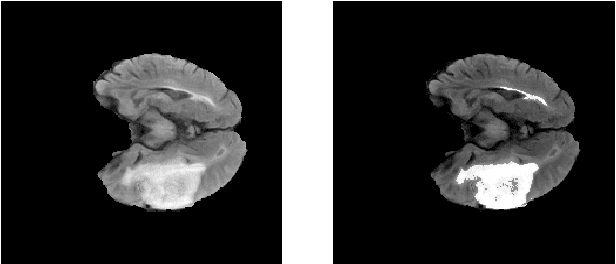

Abstract:Efficient and accurate brain ventricle segmentation from clinical CT scans is critical for emergency surgeries like ventriculostomy. With the challenges in poor soft tissue contrast and a scarcity of well-annotated databases for clinical brain CTs, we introduce a novel uncertainty-aware ventricle segmentation technique without the need of CT segmentation ground truths by leveraging diffusion-model-based domain adaptation. Specifically, our method employs the diffusion Schr\"odinger Bridge and an attention recurrent residual U-Net to capitalize on unpaired CT and MRI scans to derive automatic CT segmentation from those of the MRIs, which are more accessible. Importantly, we propose an end-to-end, joint training framework of image translation and segmentation tasks, and demonstrate its benefit over training individual tasks separately. By comparing the proposed method against similar setups using two different GAN models for domain adaptation (CycleGAN and CUT), we also reveal the advantage of diffusion models towards improved segmentation and image translation quality. With a Dice score of 0.78$\pm$0.27, our proposed method outperformed the compared methods, including SynSeg-Net, while providing intuitive uncertainty measures to further facilitate quality control of the automatic segmentation outcomes.